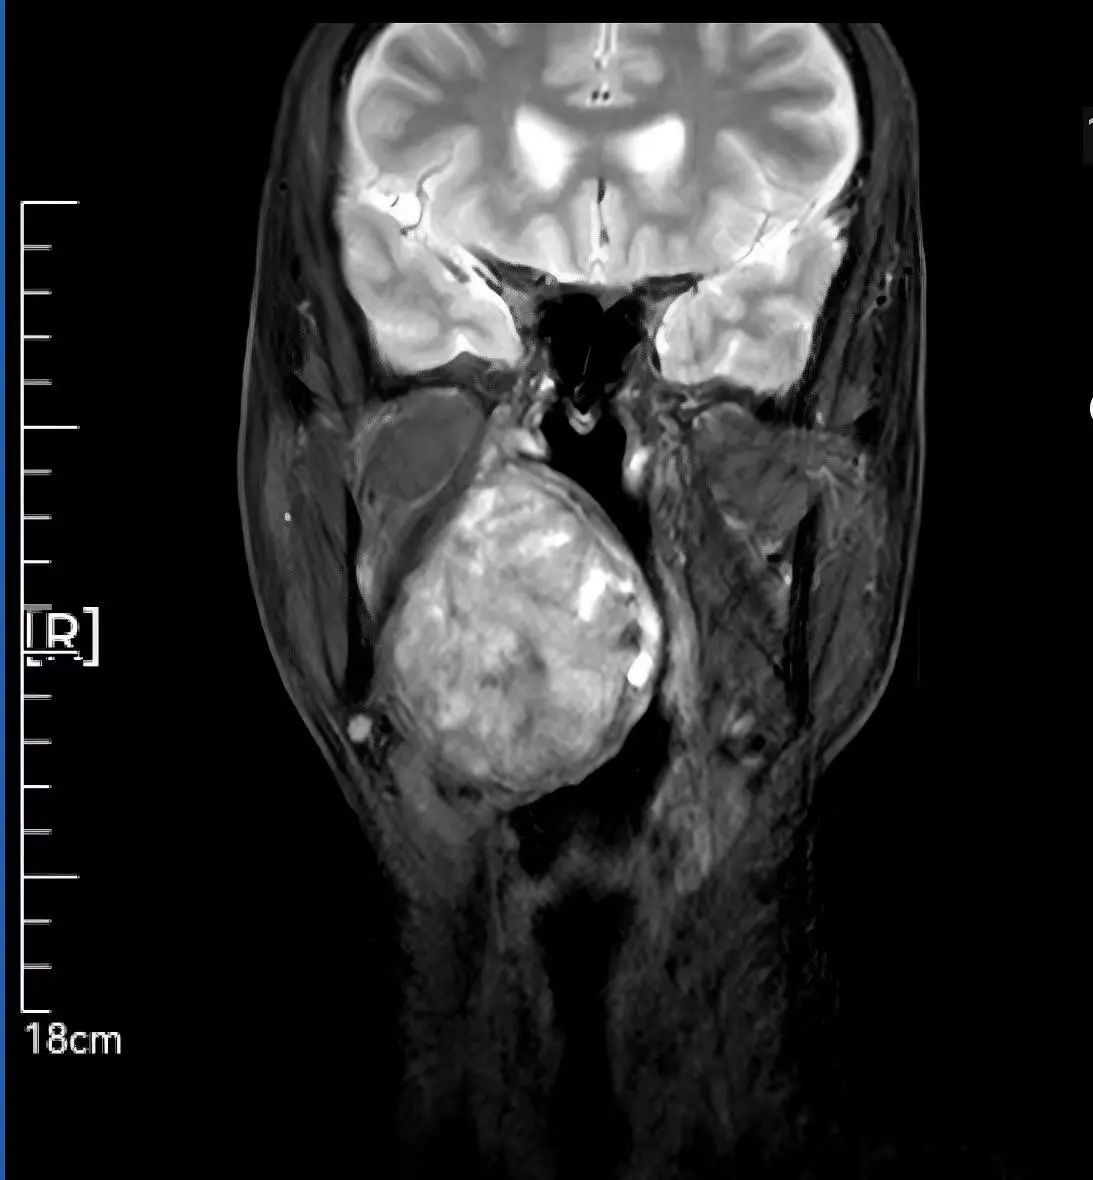

59歲患者因腭部膨隆伴吞咽呼吸困難輾轉(zhuǎn)求醫(yī),最終就診于我院頭頸外科。李智林副主任查體發(fā)現(xiàn),患者咽部明顯膨隆,懸雍垂左偏,雙側(cè)扁桃體完全被腫瘤遮蔽,口咽腔嚴重狹窄移位。影像檢查顯示,6.2×1.4×7.3cm的腫瘤深居右側(cè)咽旁間隙,穿刺病理提示,明確為涎腺來源多形性腺瘤,毗鄰頸動脈、顱底神經(jīng)群,手術(shù)風險極高。

顯微操作實施“咽喉拆彈” 三階段方案守護神經(jīng)功能 面對“手術(shù)禁區(qū)挑戰(zhàn)”,團隊制定精細化方案: 術(shù)前攻堅:利用MRI精準定位腫瘤邊界,制定血管神經(jīng)保護預(yù)案; 術(shù)中突破:先行氣管切開建立生命通道,經(jīng)下頜骨劈開入路顯微分離腫瘤,完整保留頸內(nèi)動脈、面神經(jīng)等重要結(jié)構(gòu); 功能重建:以鈦板固定下頜骨,最大程度恢復咀嚼功能與面部形態(tài)。 歷經(jīng)數(shù)小時顯微操作,最終實現(xiàn)了腫瘤的根治性完整切除,并奇跡般地完整保住了患者的局部核心結(jié)構(gòu)和重要神經(jīng)功能。 可視化溝通破疑慮 從“被動治療”到“主動共信” 面對下頜骨劈開的手術(shù)方案,患者對創(chuàng)傷及并發(fā)癥充滿擔憂。李智林副主任創(chuàng)新采用“模型+預(yù)案”可視化溝通模式,直觀演示手術(shù)路徑,并針對患者對切口美觀的需求優(yōu)化入路設(shè)計。通過“治療方案共決策”機制,患者全程參與診療討論,最終從“被動接受”轉(zhuǎn)為“主動信任”。術(shù)后,在護士長范改萍及病區(qū)護士長李霞護理團隊的精細照料下,患者恢復良好,吞咽和呼吸功能逐漸改善,目前已順利康復出院。 “是你們給了我第二次生命,頭頸外科團隊用技術(shù)解除我的病痛,用真誠治愈恐懼,這就是醫(yī)護最好的模樣。”這段樸實的感言,成為“技術(shù)救治+人文關(guān)懷”的最佳注釋。 學科引領(lǐng)賦能精準醫(yī)療 技術(shù)與溫度并重的診療范式 此次手術(shù)由頭頸外科主任李德志教授全程指導,依托科室多學科協(xié)作(MDT)體系與顯微外科技術(shù)優(yōu)勢,實現(xiàn)“精準切除-功能保留-人文關(guān)懷”三重突破。未來,團隊將以更前沿的醫(yī)療技術(shù)、更溫暖的人文關(guān)懷,不斷攀登醫(yī)學高峰,守護區(qū)域內(nèi)百姓頭頸健康,為生命安全構(gòu)筑堅實防線。